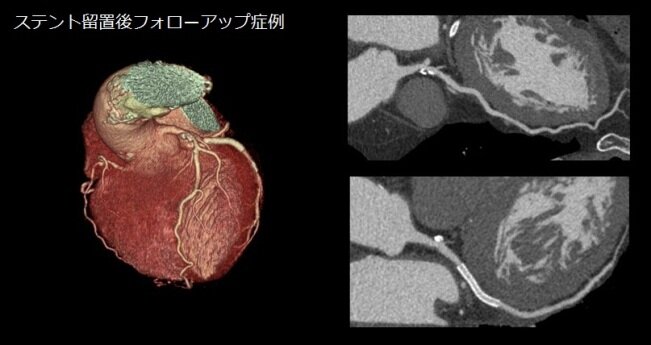

当院のCTは2016年に導入されたもので、1回転あたり最速0.28秒、最大160mm幅の撮影が可能な装置です。当時のGE社ではフラグシップモデルでしたが、装置は日々進化しています。当院では可能な限りバージョンアップを続け、見た目は導入当時とほぼ変化ありませんが、中身は2024年4月現在でもGE社の上位機種となっています。 当院で専門とする狭心症、心筋梗塞の原因となる冠動脈におこる動脈硬化による狭窄の有無を1心拍で撮影することが可能ですが、2022年のバージョンアップで、X線管球を最高品質のものに交換し、更に心臓の拍動によるブレを低減させるSnapShot Freeze2.0への更新で、冠動脈はもちろんのこと、心臓弁膜症の原因となる大動脈弁、僧帽弁の動態観察が可能となり、診断に威力を発揮しています。 |

更に、ディープラーニングを用いて開発された次世代画像再構成法TrueFidelity™ Imagingが搭載され、従来より30~50%被ばくを減らしても従来と同等もしくはそれ以上の画質が提供できます。この再構成法と「High Resolutionモード」との併用で冠動脈内に留置されたステント内部が、従来より詳細に描出することも可能です。

CTの単純画像だけではなく造影剤を使用した冠動脈や大血管の画像により適確な診断が可能となり、患者さんへの説明にも利用されて病気に対する理解を深めていただくことにも役立っております。